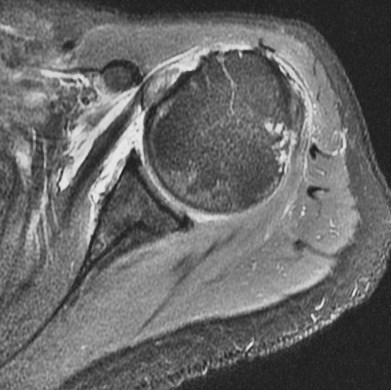

75 y/o s/p dislocation

Dislocation pathology is typically different in older patients than younger patients. The great majority of first time dislocators under the age of 40 suffer a bankart lesion (avulsion of the labral ligamentous complex on the glenoid side). Older folks often suffer a rotator cuff tear including the supraspinatus or subscapularis (or both). This patient had an SST tear but in addition also has a HAGL lesion (humeral avulsion of the glenohumeral (IGHL) ligament). She also has subscapularis partial tearing associated with a near complete dislocation of the biceps (findings that I think were preexisting). Reference article.

HAGL lesion and rotator cuff tears